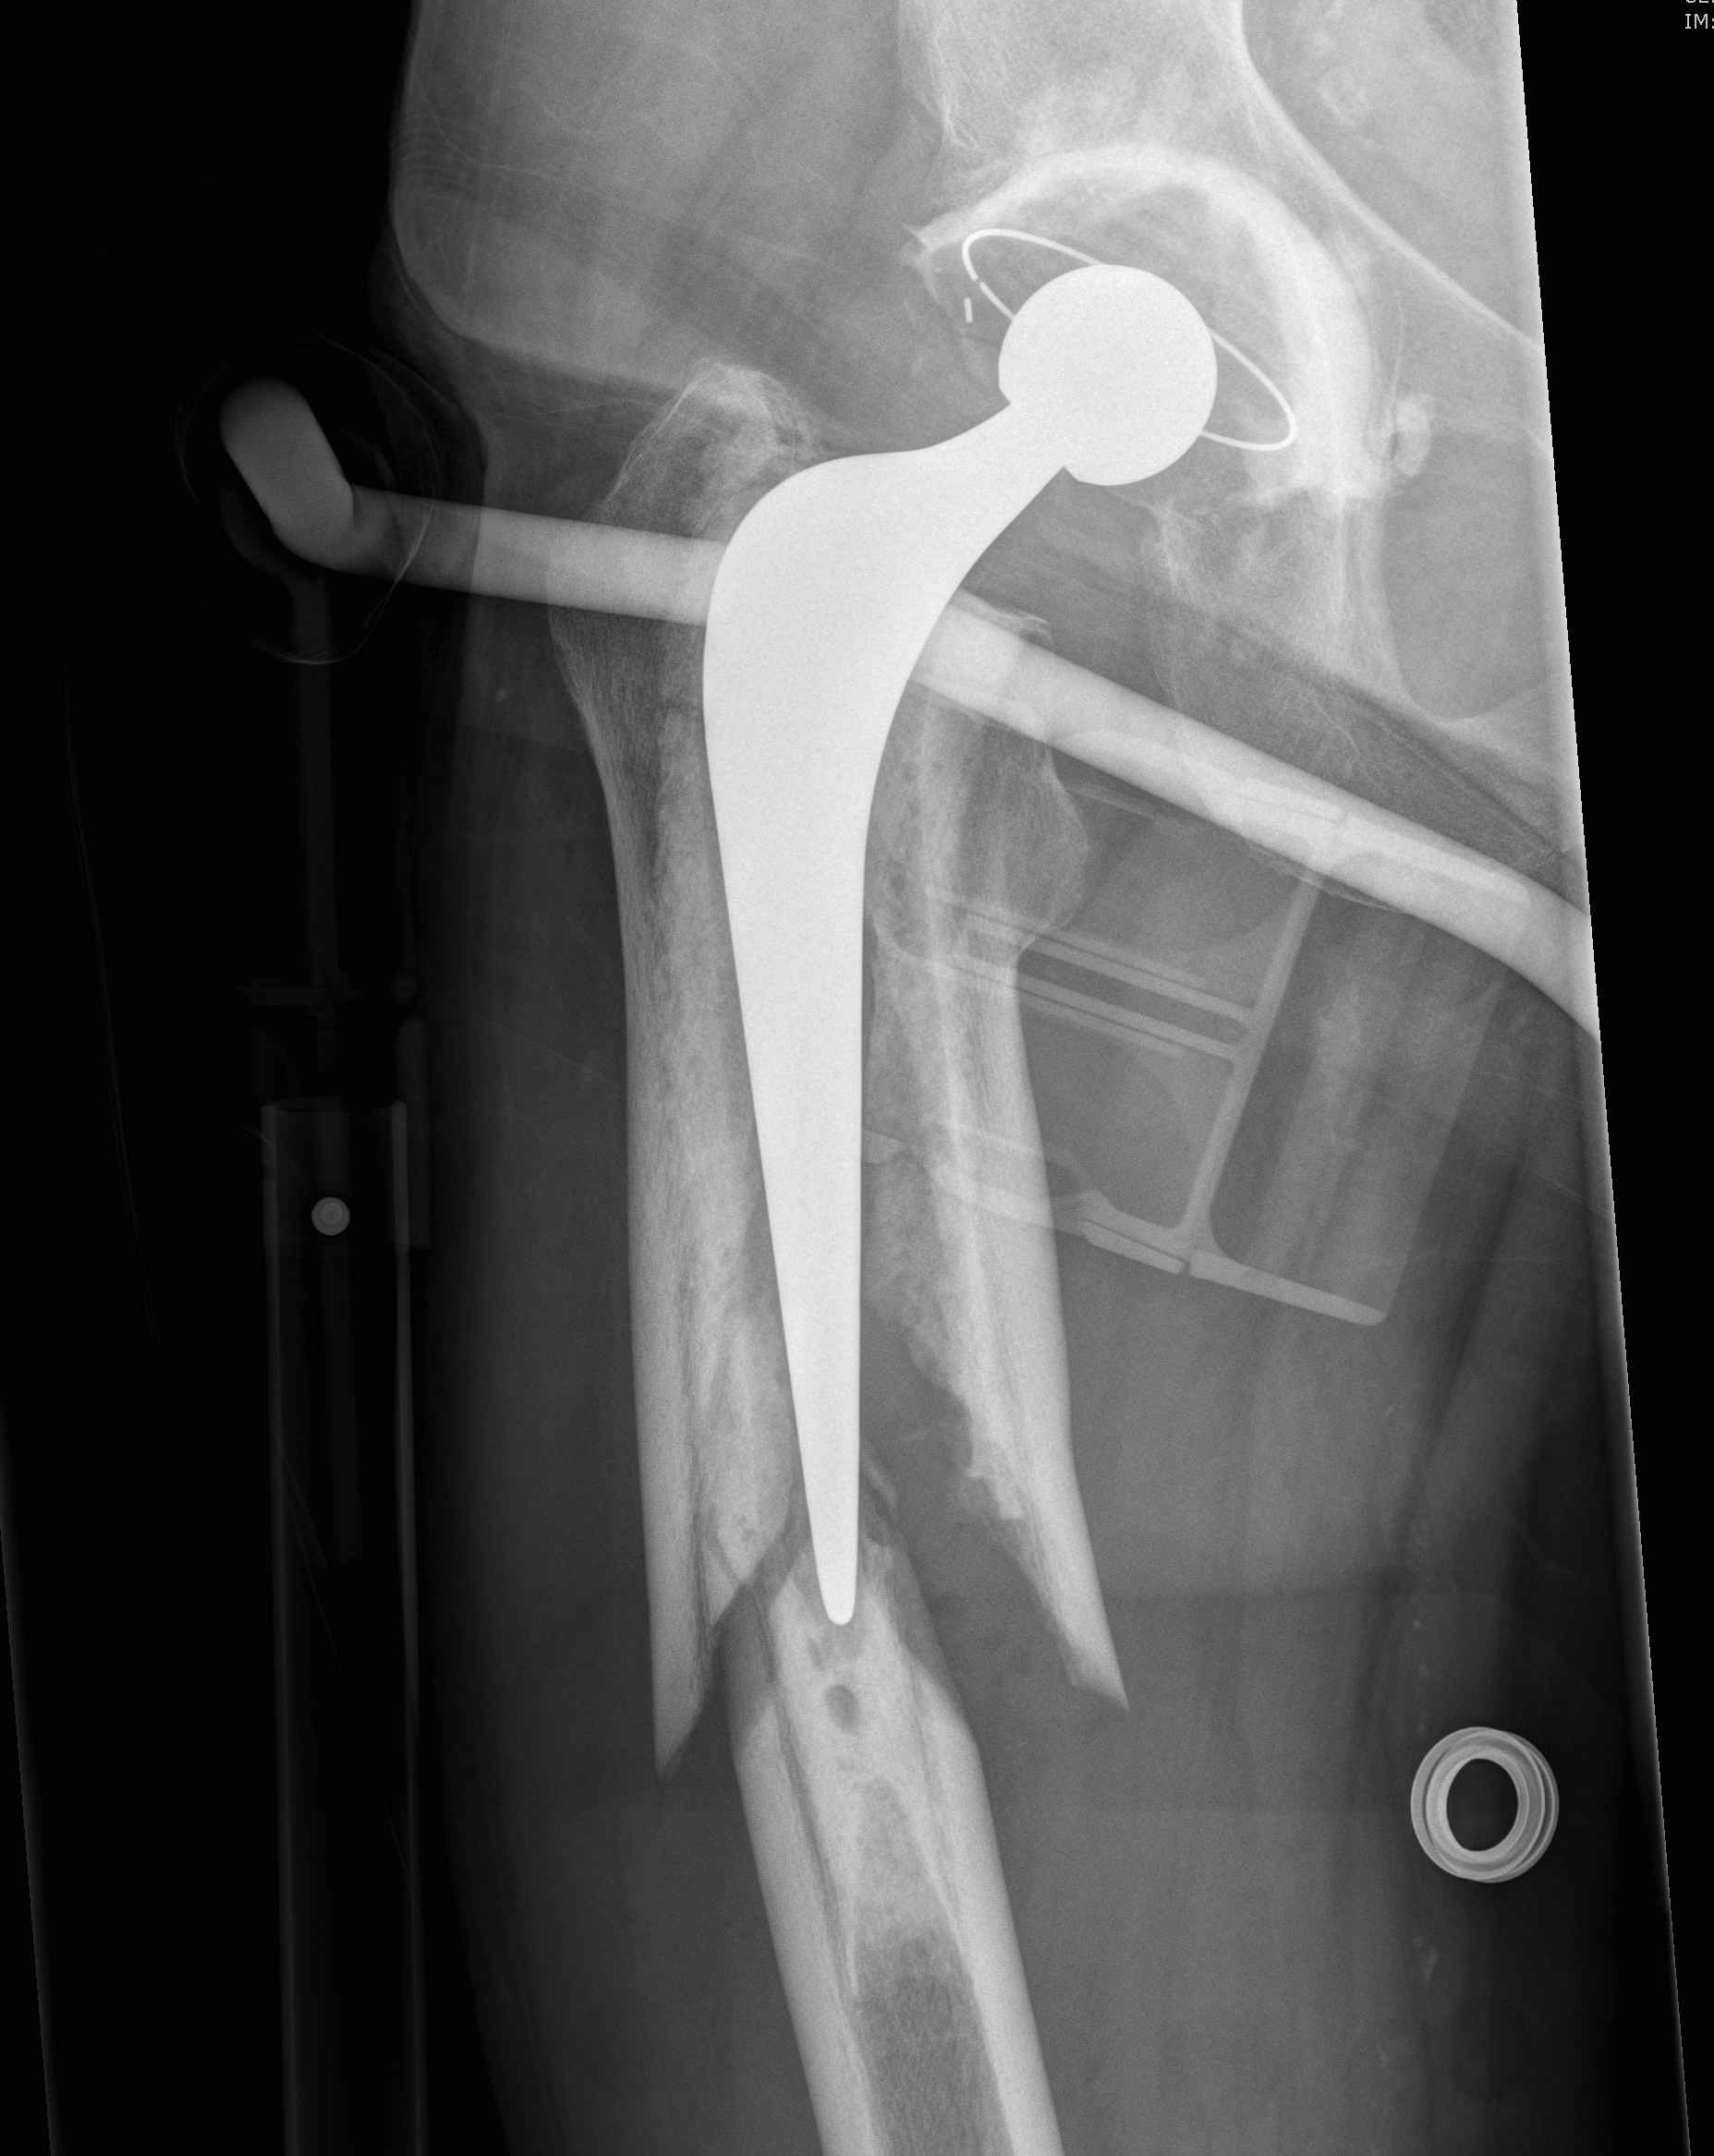

Fracture with stem subsidence around a polished tapered femoral stem treated with ORIF

B. ORIF and prosthesis retention

- cemented smooth polished taper-slip femoral stems

- bone-cement interface intact

- able to achieve anatomical reduction around stem